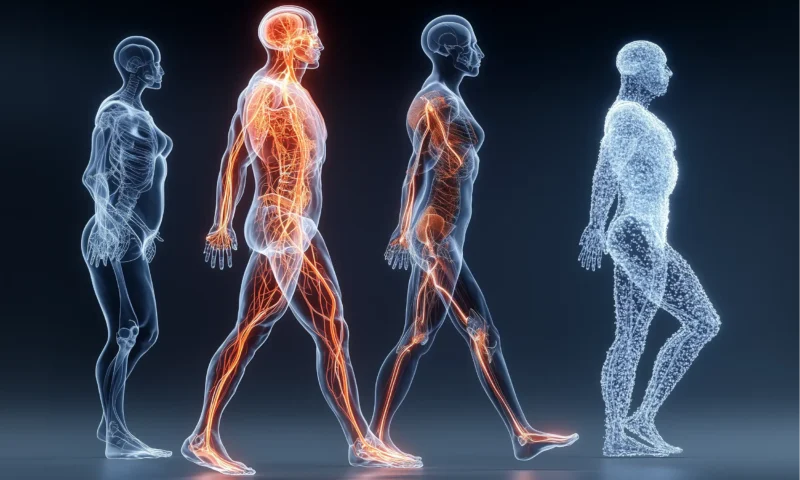

Die Orthopädie ist ein medizinisches Fachgebiet, das sich mit der Diagnose, Behandlung und Prävention von Erkrankungen, Verletzungen und Fehlbildungen des menschlichen Bewegungsapparates befasst. Dieser umfasst Knochen, Gelenke, Muskeln, Sehnen, Bänder und Nerven. Der Begriff „Orthopädie“ leitet sich vom altgriechischen „orthos“ (aufrecht, gerade) und „paideia“ (Kindererziehung) ab, was ursprünglich die Korrektur von Fehlstellungen bei Kindern, insbesondere der Wirbelsäule und der Gliedmaßen, bezeichnete. Heute ist das Fachgebiet jedoch weit umfassender und behandelt Patienten jeden Alters.

Im Kern ist die Orthopädie die Lehre vom „geraden Kind“ – eine historische Bezeichnung, die auf die ursprüngliche Fokussierung auf die Korrektur von Deformitäten bei Kindern zurückgeht. Mit der Zeit hat sich das Fachgebiet jedoch erheblich erweitert und umfasst heute die gesamte Bandbreite der muskuloskelettalen Gesundheit. Orthopäden sind darauf spezialisiert, die Funktion und Schmerzfreiheit des Bewegungsapparates wiederherzustellen und zu erhalten. Dies beinhaltet nicht nur die Behandlung akuter Probleme, sondern auch die langfristige Betreuung bei chronischen Erkrankungen und die Prävention von zukünftigen Beschwerden.